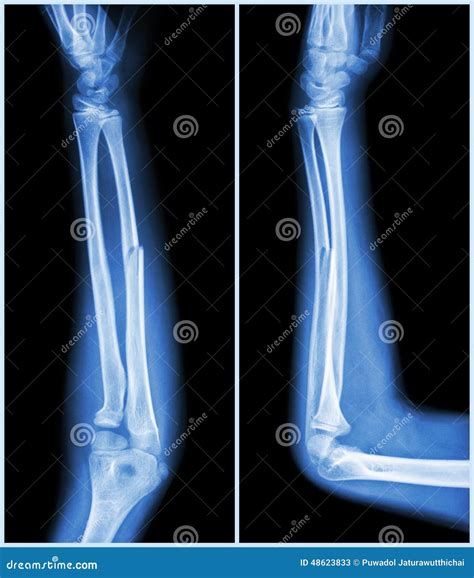

• Imaging Tests: X-rays are the primary diagnostic tool for identifying fractures. In some cases, additional imaging tests like CT scans or MRIs may be required for a more detailed view.

Imaging tests are crucial for determining the type and severity of the fracture, which will guide the treatment plan.

Types of Ulna Fractures

Ulna fractures can be classified into different types based on their location and pattern. Common types include:

• Proximal Ulna Fracture: Occurs near the elbow joint.

• Midshaft Ulna Fracture: Occurs in the middle of the ulna.

• Distal Ulna Fracture: Occurs near the wrist joint.

• Open Fracture: The bone breaks through the skin, increasing the risk of infection.

• Closed Fracture: The bone breaks but does not penetrate the skin.

• Comminuted Fracture: The bone shatters into multiple pieces.

• Greenstick Fracture: Common in children, where the bone bends and partially breaks.

Each type of fracture requires a specific approach to treatment, which will be determined by the healthcare provider.